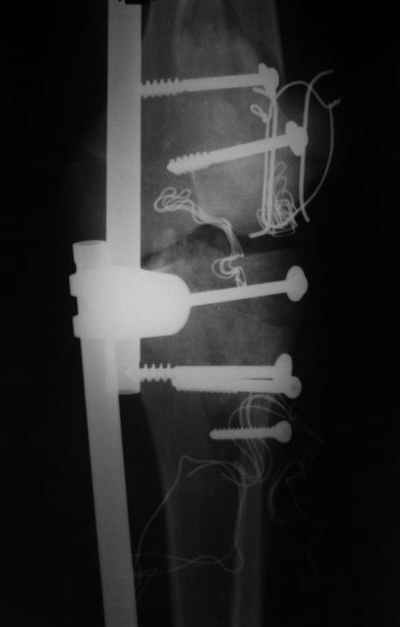

Левосин и левомиколь.... По рекомендации Джолдаса съимпровизировал вакуумное дренирование ран, посмотрим как эта система работает, картинки отправлю отдельной почтой. Некроз кожного лоскута прогрессирует.....

Вакуумное дренирование и ожидание грануляций и окончательной демаркации, посмотрим дальше, может быть, возникнет необходимость повторной обработки,

пока боли стихли, температура нормализовалась.